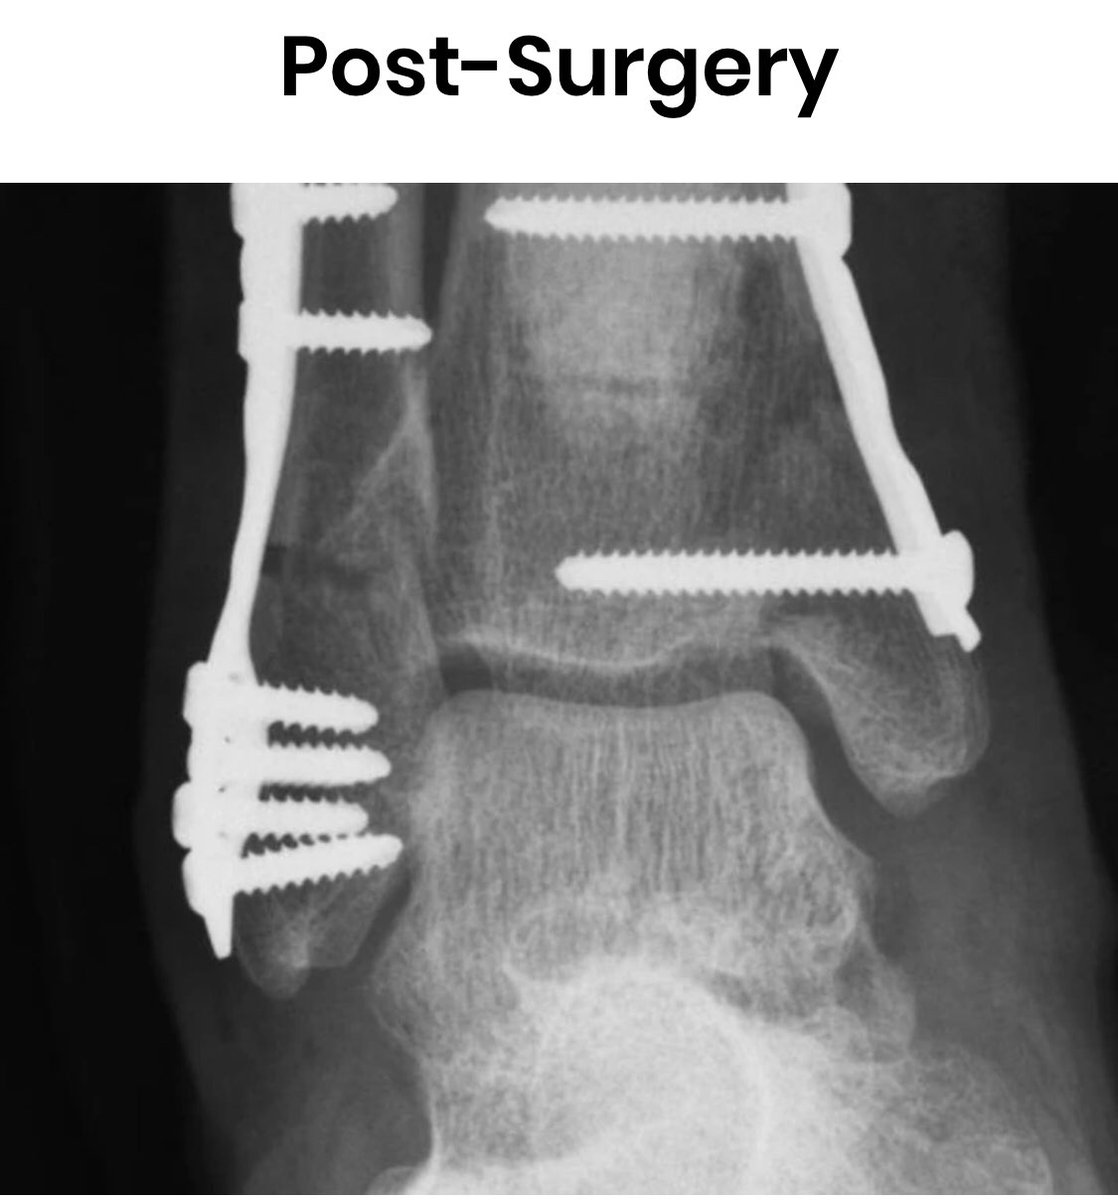

• The Cowboys didnt win Thursday nights epic passing battle between Dak Prescott and Tom Brady. Playing his first game since suffering a gruesome ankle injury 11 months ago and then signing a 160 million contract Dak Prescott was outstanding against a defense that shut down Patrick Mahomes in the Super Bowl and returned every starter. Emotional Dallas Cowboys quarterback Dak Prescott suffers GRUESOME ankle injury as hes carted off the field in tears against New York Giants. Updated 343 AM ET Wed October 14 2020. Silverman is no stranger to breaking down the forces of nature that result in an athletes injury as well as their expected recovery protocol. Orthopedic Surgeon Explains Dak Prescotts Ankle Fracture.

Dak Prescotts gruesome ankle injury will only take Dallas season from bad to worse. The bottom line is hes there. Prescott was in tears as he was carted off of the field raising a fist to the Cowboys crowd before being taken to the back for what will surely be X-rays and an MRI to determine the exact extent. Dak Prescott suffered a horrific season-ending injuring Sunday –snapping his ankle in the worst possible way requiring emergency surgery. The Dallas Cowboys QB was.

Silverman is no stranger to breaking down the forces of nature that result in an athletes injury as well as their expected recovery protocol. AP Dak is back and hes still not enough for the Dallas Cowboys. Orthopedic Surgeon Explains Dak Prescotts Ankle Fracture. The bottom line is hes there. Dak Prescott suffered a horrific season-ending injuring Sunday –snapping his ankle in the worst possible way requiring emergency surgery.

Dak Prescott Had An Unreported Second Ankle Surgery Source: thelandryhat.com